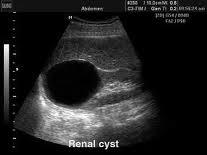

cysta renis

Az egyszerű veseciszta (folyadékkal telt tömlő) eredete a mai napig sem tisztázott pontosan. Az elváltozás többnyire egyoldali, de kétoldali is lehet és a vese bármely területén elhelyezkedhet. Gyakoriság szempontjából a legtöbbször felfedezett elváltozása a vesének. Tüneteket csak extrém méret esetén (8-15 cm), a vese vizeletelvezető rendszerének összenyomása esetén okozhat. Ilyenkor deréktáji tompa, vagy görcsös panaszok jelentkezhetnek, illetve tapinthatóvá válhat a cysta.

Amennyiben a ciszta a vesekocsány környékén helyezkedik el, parapyelaris cisztáról beszélünk. Lényegesen ritkábban találkozunk ezzel a formával, de hasonlóan a kérgi cisztához, szintén ártalmatlan jelenség.